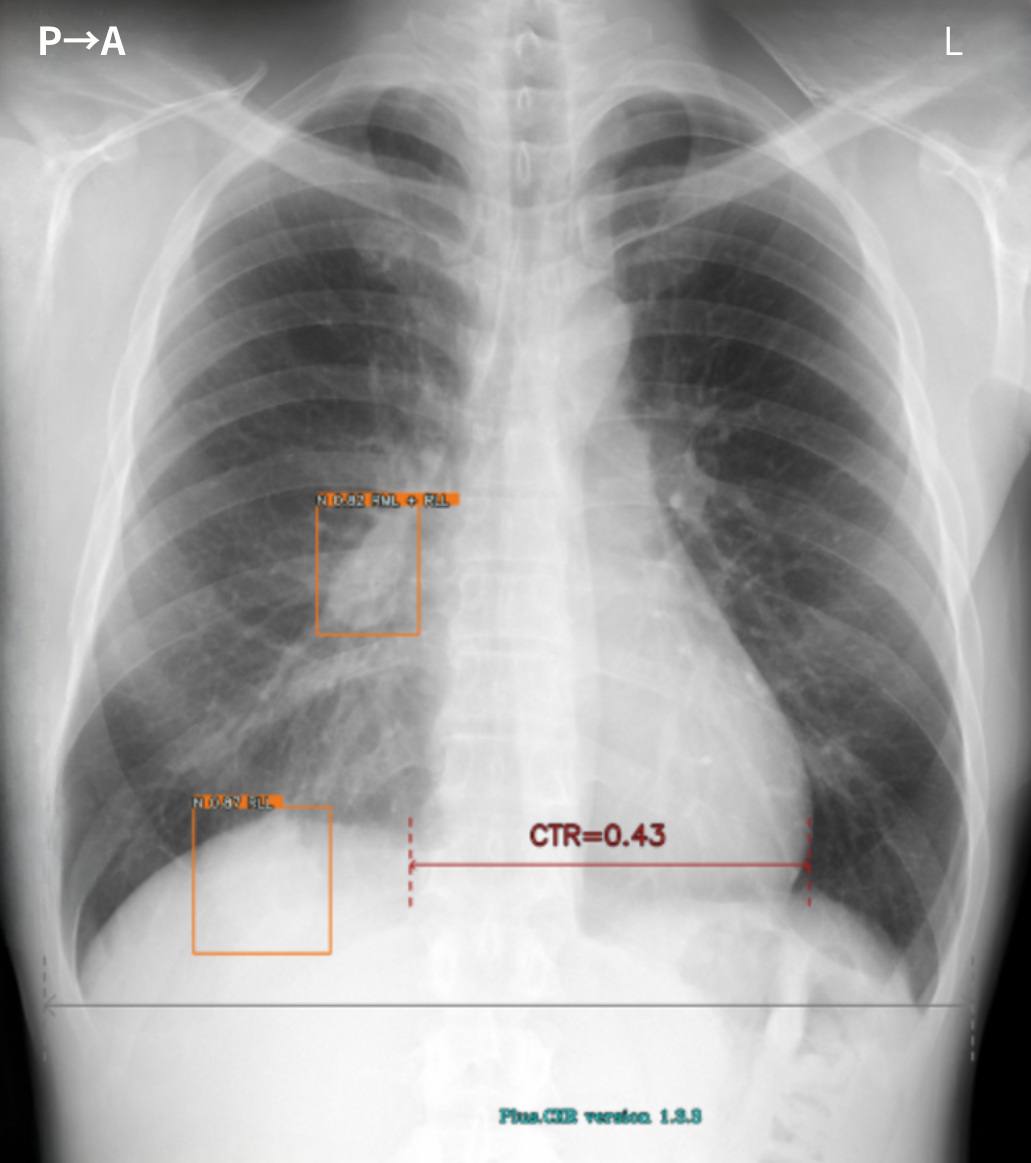

胸部X線AI「Plus.CXR」が指摘する、正常な乳頭陰影や肋骨肋軟骨移行部周囲の軟骨の骨化(Ossification)、各所の胸膜肥厚所見などの精査不要の陰性所見をより短時間でルールアウトできるようになりました。

また、胸部X線AI「Plus.CXR」では著者が通常は指摘できない、径5mm前後の比較的小さな病変を指摘できます。

加えて、肺門部周囲の太い血管陰影とシルエットが明瞭に存在する淡い透過性の低下部を指摘することができました。これらは、十分な集中力で画像を参照していない場合見落とす可能性が高い所見だと思料されます(図1,2,3)。